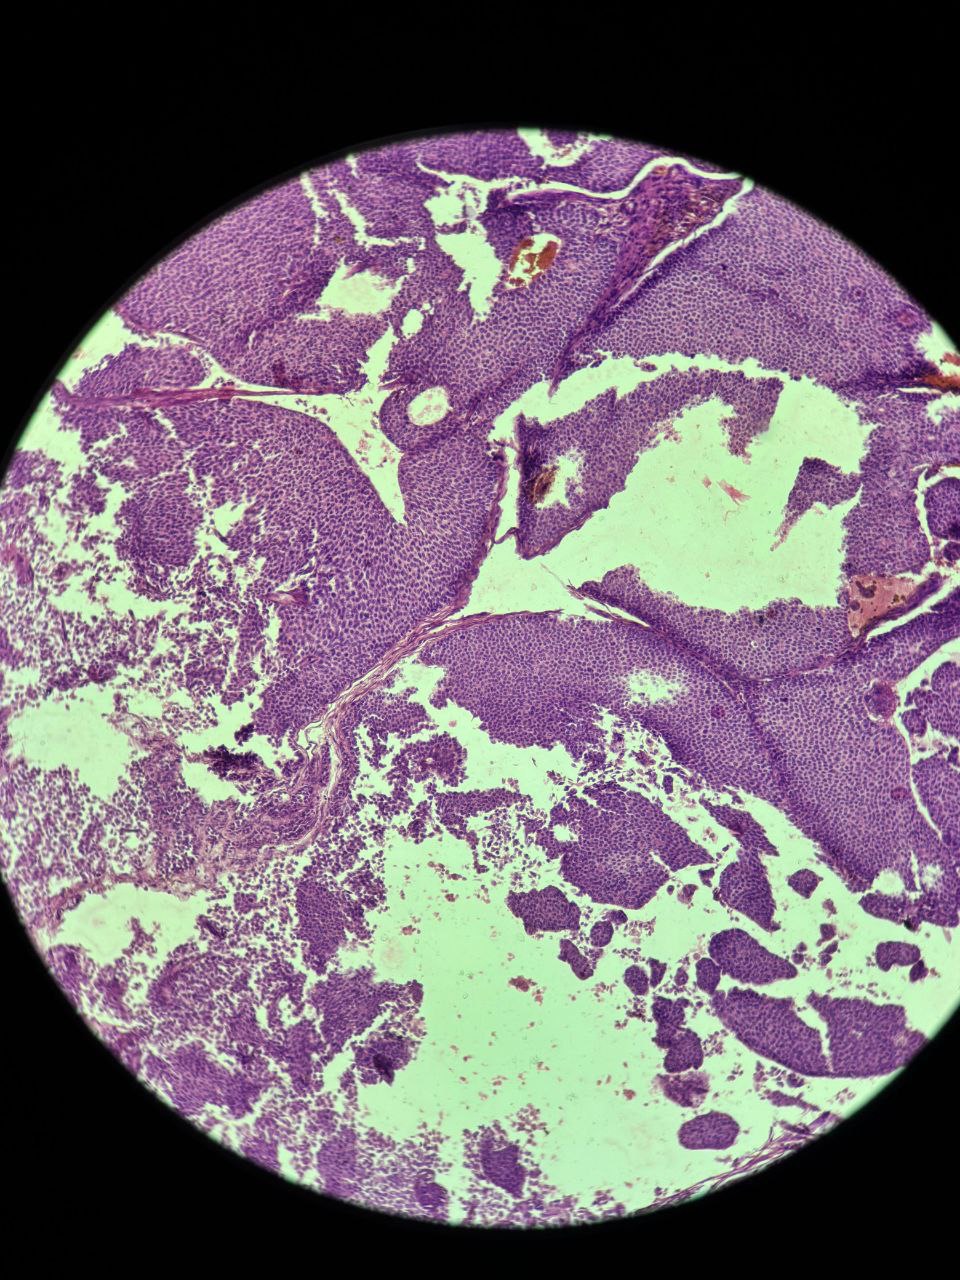

The patient underwent a Modified Radical Mastectomy with axillary dissection. Histopathological examination confirmed the diagnosis of Invasive Solid Papillary Carcinoma. The tumor was located in the retro-areolar region, measuring 7 × 5 × 2.5 cm. Microscopically, expansile nodules composed of a solid epithelial proliferation punctuated by delicate fibrovascular cores were noted (Figure 1). The epithelial proliferation had monomorphic, round to oval and plasmacytoid tumor cells with low to intermediate grade nuclear atypia (Figure 2). Infiltration into the surrounding adipose tissue was noted along with focal lymph vascular space invasion (LVSI). All surgical margins were free of tumor. One out of the twelve resected lymph nodes were positive for tumor cells. IHC revealed strong reactivity for cytokeratin (CK7), Epithelial Membrane Antigen (EMA) and Progesterone Receptor (PR), with negative immunostaining for chromogranin, synaptophysin, p63, CD 56, ER, and Her-2 neu.

Figure 1. Microscopic histopathological appearance showing expansile nodules composed of a solid epithelial proliferation, punctuated by delicate fibrovascular cores.